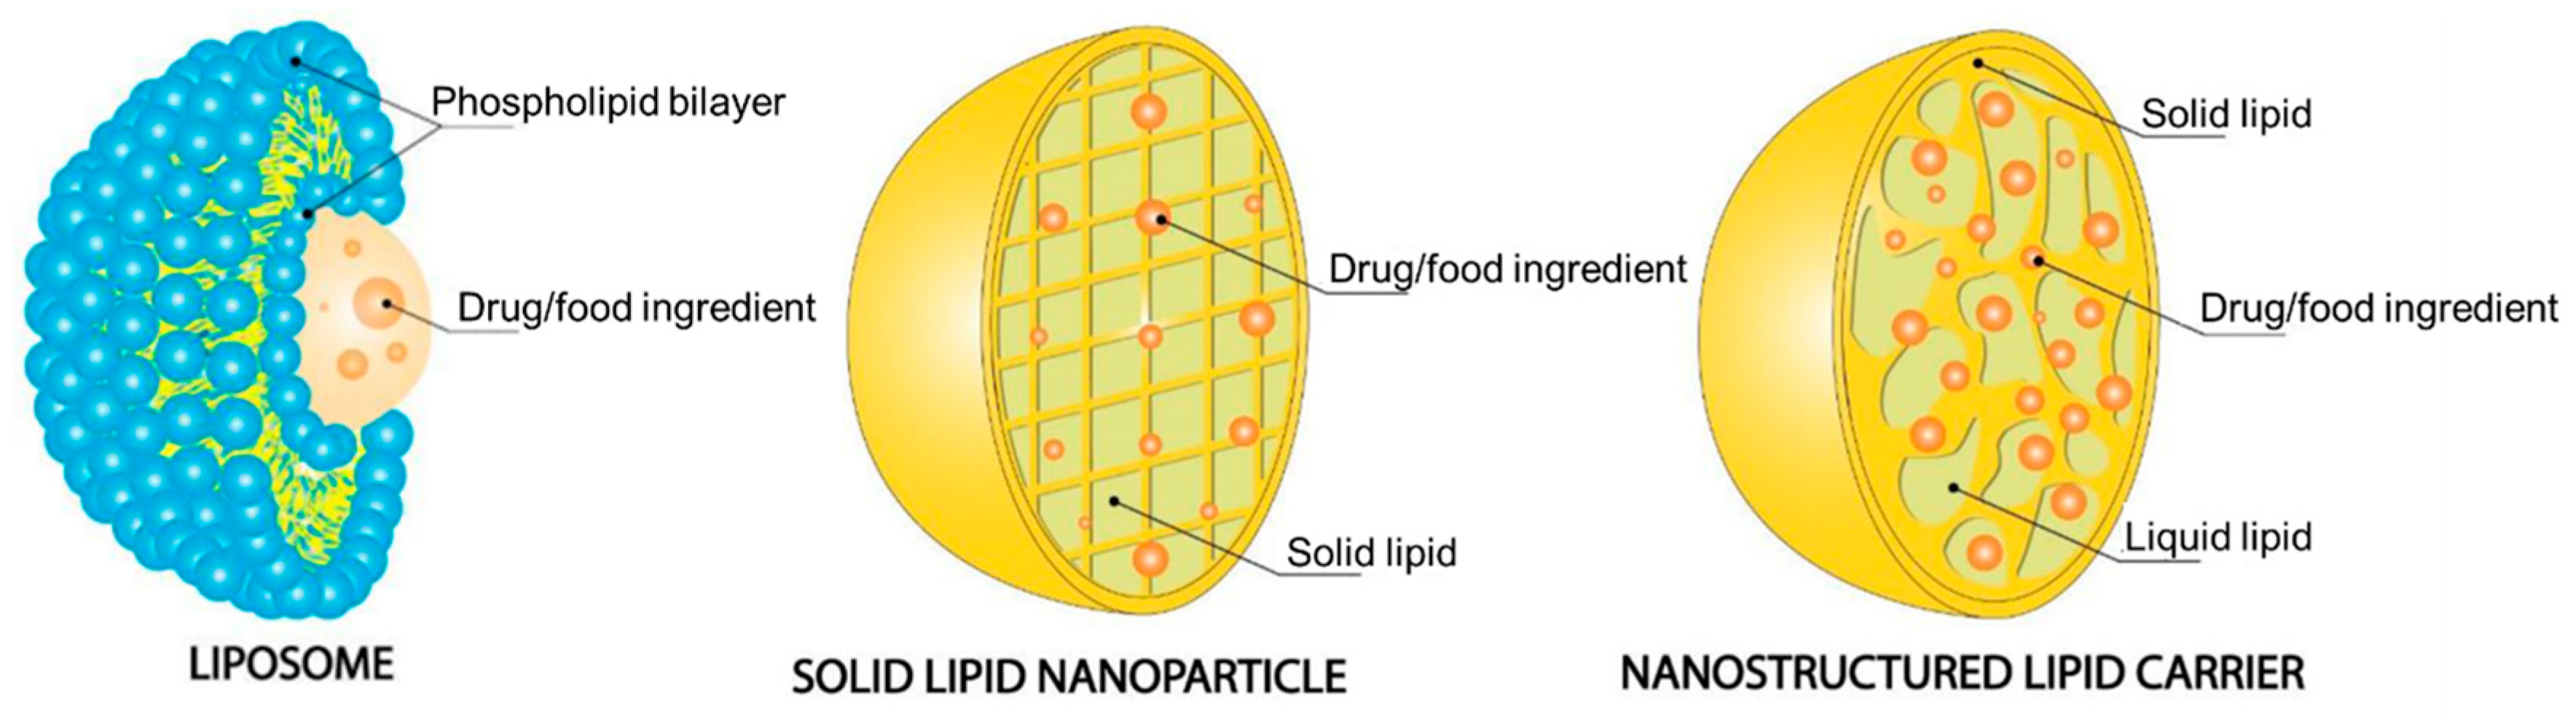

7.1. Lipid-Based Nanoparticles

7.1.1. Liposomes

7.1.2. Solid Lipid Nanoparticles

7.1.3. Nanostructured Lipid Carriers

- Barroso, L.; Viegas, C.; Vieira, J.; Ferreira-Pêgo, C.; Costa, J.; Fonte, P. Lipid-Based Carriers for Food Ingredients Delivery. J. Food Eng. 2021, 295, 110451. [Google Scholar] [CrossRef]

- Viegas, C.; Seck, F.; Fonte, P. An Insight on Lipid Nanoparticles for Therapeutic Proteins Delivery. J. Drug Deliv. Sci. Technol. 2022, 77, 103839. [Google Scholar] [CrossRef]

- Viegas, C.; Patrício, A.B.; Prata, J.M.; Nadhman, A.; Chintamaneni, P.K.; Fonte, P. Solid Lipid Nanoparticles vs. Nanostructured Lipid Carriers: A Comparative Review. Pharmaceutics 2023, 15, 1593. [Google Scholar] [CrossRef] [PubMed]

- Haider, M.; Abdin, S.M.; Kamal, L.; Orive, G. Nanostructured Lipid Carriers for Delivery of Chemotherapeutics: A Review. Pharmaceutics 2020, 12, 288. [Google Scholar] [CrossRef] [PubMed]

- Müller, R.H.; Radtke, M.; Wissing, S.A. Nanostructured Lipid Matrices for Improved Microencapsulation of Drugs. Int. J. Pharm. 2002, 242, 121–128. [Google Scholar] [CrossRef]